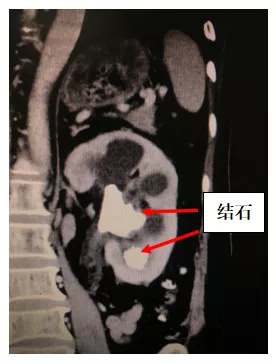

接诊后,俞国锋主任为其详细查体,发现患者体温38.0℃,精神相当萎靡,贫血貌,血红蛋白87g/l。检查CTU后显示双肾铸型结石、双肾积水,左肾盂、肾盏铸型结石4.0cm*3.0cm伴嵌顿,左肾区叩痛明显。

术前CT

在俞国锋带领下,泌尿系结石团队对任女士的病情仔细研究,诊断为:双肾结石、双肾积水伴严重感染,左侧脓肾,需立即行左侧脓肾引流、经皮肾穿刺造瘘术或输尿管镜下置DJ管术。但由于其左肾盂、肾盏铸型大结石嵌顿紧密,置入DJ管的可能性较小,而在铸型结石没有完全被击碎打开前,行经皮肾穿刺造瘘术的引流效果欠佳。如果在感染未完全控制下,直接行经皮肾镜取石术清除结石,由于结石负荷大、手术耗时长,手术风险极高,术中、术后还易出现尿源性脓毒血症,甚至多功能脏器衰竭、死亡。面对上述情况,俞国锋主任再次对病情进行评估,决定先予以敏感抗生素抗感染3天,再分期进行手术。